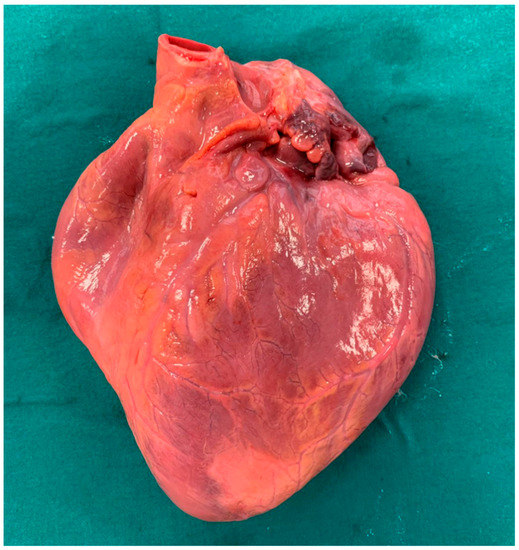

2. Case Report

6.1. Autopsy Findings